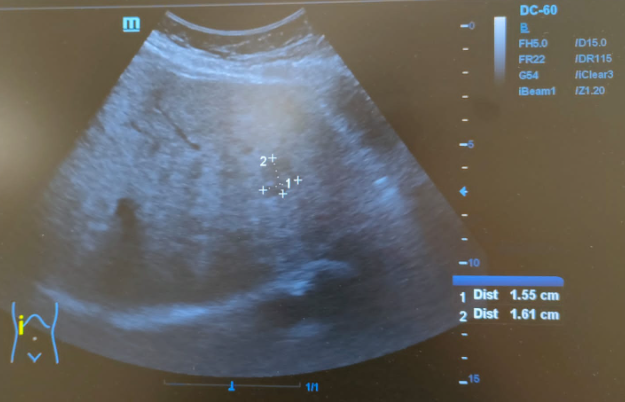

Hallazgos ecográficos

Hígado de tamaño normal, contornos ligeramente nodulares, alteración de la ecoestructura compatible con hepatopatía crónica. Nódulo hipoecoico de contornos irregulares en lóbulo hepático izquierdo de 16x24mm sin captación Doppler.

Tras realizar la ecografía en el CAP se observó un nódulo hipoecoico de contornos irregulares. Entre los diagnósticos diferenciales posibles que justificasen el patrón de colestasis se encontraba el CHC o una metástasis, por lo que se realizó una prueba complementaria que confirmó el diagnóstico de CHC.